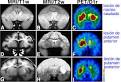

1. Alzheimer

1. Modelo del ratón transgenito de la enfermedad de alzheimer